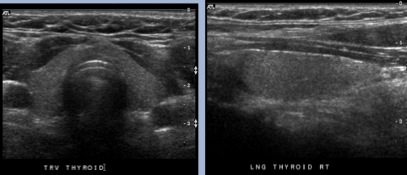

Dx?

Normal thyroid US